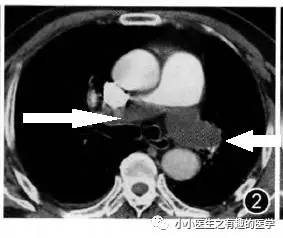

血栓太小了?来几个大的给你看看。首先,看看大扯蛋血栓。医学上,有种血栓叫骑跨血栓,很危险,骑跨:听着很拗口,也不形象,叫扯蛋血栓更形象。

部分学者认为骑跨血栓风险高,即使血流动力学稳定(无休克、血压下降等)也应该给予强有力的治疗:外科手术取栓、介入取栓、溶栓治疗,迅速溶解血栓恢复肺循环血流。真是扯着蛋了。

广州呼研所报道的一例:扯蛋血栓。

入院后给予伊诺肝素钠皮下注射,第2天患者气促较前加重。体检:呼吸27次/分,Sp02:90%(吸氧4 L/min),血压103/62 mmHg。家属签署同意书后,给予重组人组织纤维蛋白溶酶原激活物50mg,静脉滴注2 小时,溶栓后患者气促缓解。

治疗后复查,血栓基本溶解。